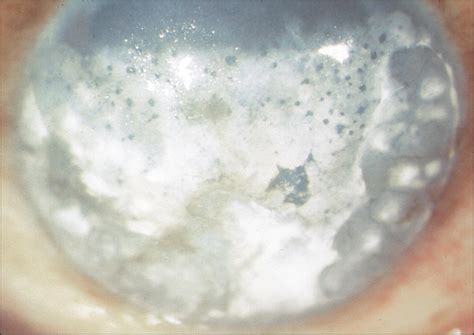

• Corneal Calcification: A more serious condition where calcium deposits form on the surface of the cornea, often appearing as a white, band-like opacity (Band Keratopathy).

• Topical Medications: In cases of corneal calcification (Band Keratopathy), doctors may use chelating agents like EDTA, which help dissolve the calcium deposits.

• Surgical Intervention: For extensive calcification that significantly impacts vision, procedures such as superficial keratectomy may be recommended to polish the corneal surface.